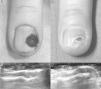

Descripción de la técnicaUna mujer de 43 años, intervenida previamente de un tumor glómico subungueal en el cuarto dedo de la mano derecha mediante la misma técnica que posteriormente se detalla, pero sin control ecográfico preoperatorio, acudió a consultas por dolor paroxístico intenso. La exploración clínica fue normal, sin evidencia de recidiva de tumor glómico subungueal (fig. 1A). Se realizó una ecografía cutánea con sonda de 18Mhz con diagnóstico de recidiva del tumor en el lecho ungueal de 3,1mm de tamaño (fig. 1B). Previo a la cirugía se localizó ecográficamente el tumor y se realizó marcaje de la lámina ungueal utilizando una guía de fabricación «casera» (fig. 2A) Para ello se mantuvo la sonda ecográfica longitudinal al aparato ungueal e introducimos la guía ecográfica perpendicular a la sonda produciéndose una reverberación en cola de cometa que nos ocultará el tumor (fig. 2B). En este punto, mantenemos la guía ecográfica fija, retiramos la sonda y realizamos el marcaje de la lámina ungueal (fig. 2C).

Posteriormente, tras realizar anestesia troncular del dedo con mepivacaína al 2% se llevó a cabo un abordaje mínimamente invasivo mediante la extirpación de la lámina ungueal con un punch de 5mm, exéresis del tumor mediante punch 4mm, disección utilizando un bisturí del n.°15, electrocoagulación del lecho ungueal y hemostasia mediante Gelita® y solución de Monsel (subsulfato férrico al 20%). En el estudio histológico se confirmó el diagnóstico de recidiva de tumor glómico. La evolución posquirúrgica de la paciente fue favorable, con desaparición del dolor tras el procedimiento y sin evidencia ecográfica de persistencia tumoral (fig. 3A-D).